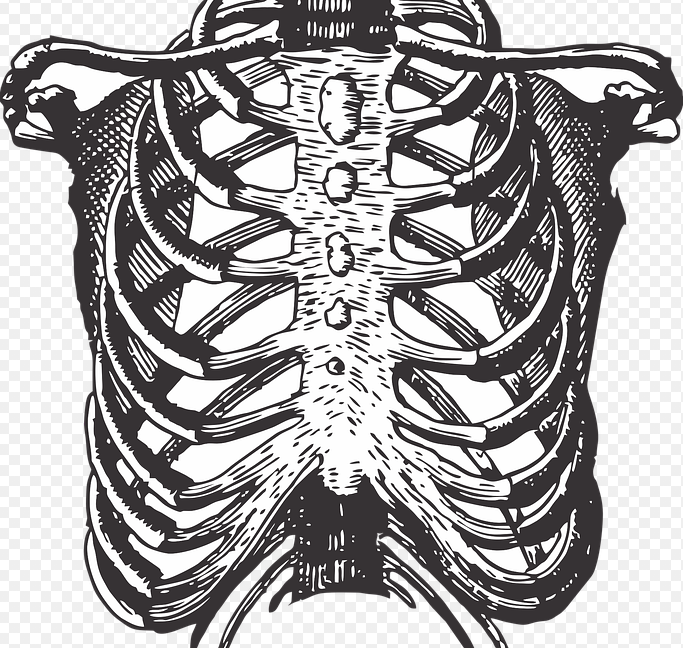

가만히 있다가 아니면 누워있다가 급하게 일어날때 또는 운동을 열심히하고 숨을 헐떡이거나 할때등 이 글을 읽으시는 분들은 한번쯤 왼쪽갈비뼈 아래에서 통증을 느껴보셨을텐데요. 저도 갑자기 허리를 못필만큼 왼쪽갈비뼈 아래에 통증이 있어서 아파본 경험이 있습니다. 금방 괜찮아져서 병원을 가진 않았지만 통증이 반복된다던가 주기적으로 또는 너무 많이 아프시면 병원에서 진료를 받는걸 추천드립니다. 그래서 오늘은 왼쪽갈비뼈 아래 통증이 왜 생기는지 궁금해서 알아봤습니다.

왼쪽갈비뼈 아래 통증 원인 10가지